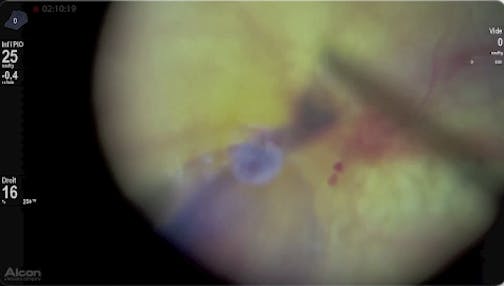

Myopic Macularschisis

Ehab El Rayes, MD